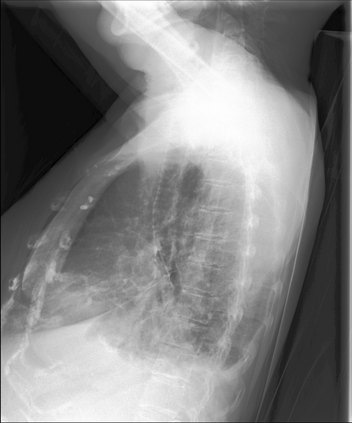

The latest breakthroughs in large vision-language models, such as Bard and GPT-4, have showcased extraordinary abilities in performing a wide range of tasks. Such models are trained on massive datasets comprising billions of public image-text pairs with diverse tasks. However, their performance on task-specific domains, such as radiology, is still under-investigated and potentially limited due to a lack of sophistication in understanding biomedical images. On the other hand, conversational medical models have exhibited remarkable success but have mainly focused on text-based analysis. In this paper, we introduce XrayGPT, a novel conversational medical vision-language model that can analyze and answer open-ended questions about chest radiographs. Specifically, we align both medical visual encoder (MedClip) with a fine-tuned large language model (Vicuna), using a simple linear transformation. This alignment enables our model to possess exceptional visual conversation abilities, grounded in a deep understanding of radiographs and medical domain knowledge. To enhance the performance of LLMs in the medical context, we generate ~217k interactive and high-quality summaries from free-text radiology reports. These summaries serve to enhance the performance of LLMs through the fine-tuning process. Our approach opens up new avenues the research for advancing the automated analysis of chest radiographs. Our open-source demos, models, and instruction sets are available at: https://github.com/mbzuai-oryx/XrayGPT.